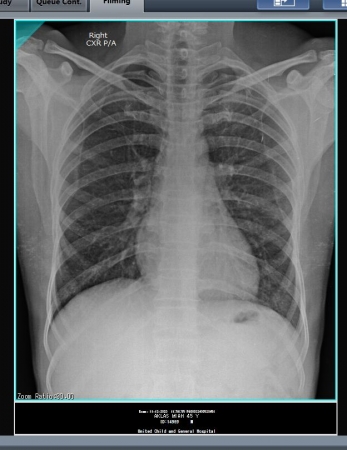

ইহা একটি বুকের এক্সরে। যাকে ডাক্তারী বাসায় বলা হয় Chest Posterior/Anterior Viwe.

রোগীর নামঃ সুগেরা বেগম। বয়সঃ ৫০ বছর।

রোগীটি নিজেও জানে না সে করোনা আক্রান্ত, সার্জারী ডাক্তার দেখাতে এসেছিল এবং গল ব্লাডার এর অপারেশন জন্য প্রস্তুতি নিচ্ছিলো। ডাক্তার তার স্বাস্থ্যের সকল অবস্থা দেখার জন্য কিছু রক্ত পরিক্ষার সাথে এই এক্সরে টি দিয়েছিল। পরীক্ষাটি করার পর আমি রীতিমতো অবাক হয়ে গেলাম। রিপোর্ট টি ডাঃ অরুন কুমার পাল কে দেখালাম। তিনি অতিদ্রুত সদর হাসপাতাল এ করোনা ইউনিটে পাঠিয়ে দিলেন।

আসুন সচেতন হই। এবং নিয়মিত স্বাস্থ্য পরিক্ষা করে দেহের ভেতরের সকল অংশের খোজ খবর রাখি। যে পরীক্ষাটি করালে আপনারা মোটামোটি ধারণা পাবেন, বা আপনার ফুসফুসে করোনা ভাইরাসের উপস্থিতি আছে কি নেই। সেটি হলোঃ CXR P/A Viwe. কারণ ভাইরাসটির প্রধান খাবার হচ্ছে ফুসফুস বা LUNGS ।আর এই পরিক্ষাটি জুড়েই রয়েছে ফুসফুসের অবস্থান।

আপনাদের বোঝার সুবিধার্থে আক্রান্ত রোগীর বুক ও সাধারণ রোগীর বুকের দুইটি এক্সরের ছবি নিচে দেওয়া হলোঃ

সাধারণ রোগীর ফুসফুস বা LUNGS ।